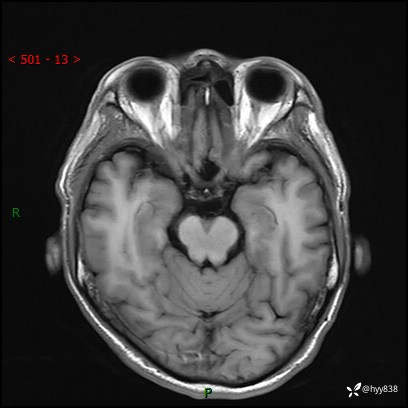

颅脑MRI平扫